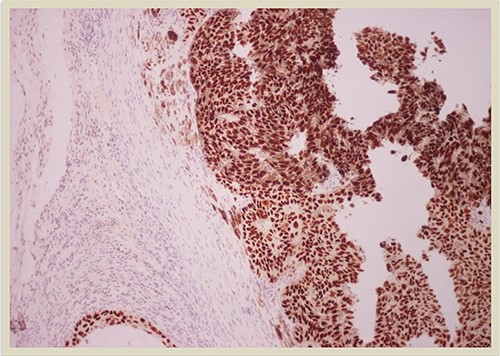

A 69-year-old man was admitted to our hospital with a nodular skin tumor of the back (Fig. 1). The patient had no ongologic history. We performed excisional biopsy that revealed collision tumor. The collision tumor consisted of mixed melanosquamous tumor (dermal squamomelanocytic tumor) together with BCC (Fig. 2). The BCC was superficial spreading. The mixed element contained squamous cell carcinoma of well/moderately differentiated and a neoplasm with melanotic characteristics, which due to cell atypia, presence of mitoses and high index of cell proliferation (Ki67: 80%) was described as melanoma (Fig. 3). Diagnosis of the melanotic and the squamous element was confirmed with immunohistochemistry (Figs 4 and 5).

HMB45 × 4: HMB45 immunostain highlights the malignant melanocytic component ( ×10 magnification).